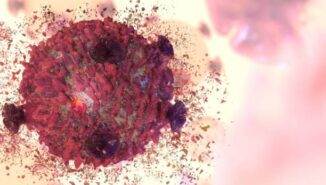

Lösemi; hastalığın ilerleyiş seyrine ve bozulmaya uğramış kan hücresinin türüne göre kronik lösemi ve akut lösemi şeklinde ikiye ayrılmaktadır. Bu genel ayrım da kendi içinde dallara ayrılmaktadır.

Akut lösemi; ağır belirtileri bir anda ortaya çıkan, vücutta hızlı bir şekilde ilerleyip birkaç gün ya da birkaç hafta gibi kısa sürede 4. evre ile karşı karşıya bırakan lösemi çeşididir. Akut lösemi kendi arasında ikiye ayrılır:

Kemik iliğinde üretilen lökositlerden (beyaz kan hücrelerinden) olan lenfositlerin, henüz olgunlaşmamış olan haline lenfoblast denir. Bu lenfoblastların olgunlaşamaması ve bu olgunlaşmamış hücrelerin kontrolsüz bir şekilde çoğalıp kana geçmesi ise kan değerlerini bozarak akut lenfoblastik lösemi‘yi oluşturur.

Kemik iliğinde üretilen lökositlerden (beyaz kan hücrelerinden) olan granülosit ve monositlern henüz olgunlaşmamış haline blast adı verilir. Bu işlev görmeyen genç hücreler aşama aşama olgunlaşır ve bağışıklığa katkı sağlar. Ancak bazı durumlarda bu genç hücreler olgunlaşamaz ve çok kontrolsüz bir şekilde üreyip kanda birikim yapar. Bu da akut miyeloid lösemi‘yi oluşturur.

Kronik lösemi ise çok geniş bir zaman yayılabilen yavaş ve sinsi bir şekilde ilerleyen lösemi çeşididir. Zaman içerisinde pek çok kişinin dikkate almayacağı belirtiler yaşatır. Hafif yorgunluklar, iştahsızlık gibi çok da dikkate alınmayan basit semptomlar belki de kronik löseminin habercisi olabilir. Ne kadar hızlı ilerleyeceği kişinin bünyesine, yaşam tarzına ve çevresinde bulunan etkenlere göre değişiklik gösterebilir. Genellikle rutin kan testlerinde tesadüfen rastlanır. (Bu şekilde erken evrede yakalanabilmesi mümkündür.) Kronik lösemi de kendi arasında iki gruba ayrılır:

Beyaz kan hücresi de denilebilen lökositlerin, lenfosit isimli alt tipinde meydana gelen mutasyondan dolayı oluşan kanserleşmeyi ifade eder. (kronik lenfositer lösemi hakkında daha fazla detay için kronik lenfositer lösemi yazısına göz atabilirsiniz.)

Lenfosit, granülosit ve monositerden oluşan lökositlerin (beyaz kan hücrelerinin) granülosit tipinde meydana gelen kanserleşmeyi ifade eder. Kanserleşmiş granülositler kontrolsüz bir şekilde ürer ve kanda birikim yapar. Ayrıca bu durum, kanda pıhtılaşmayı sağlayan trombositlerin de sayısını arttırır. Daha fazla detay için Kronik miyeloid lösemi yazısına bakabilirsiniz.